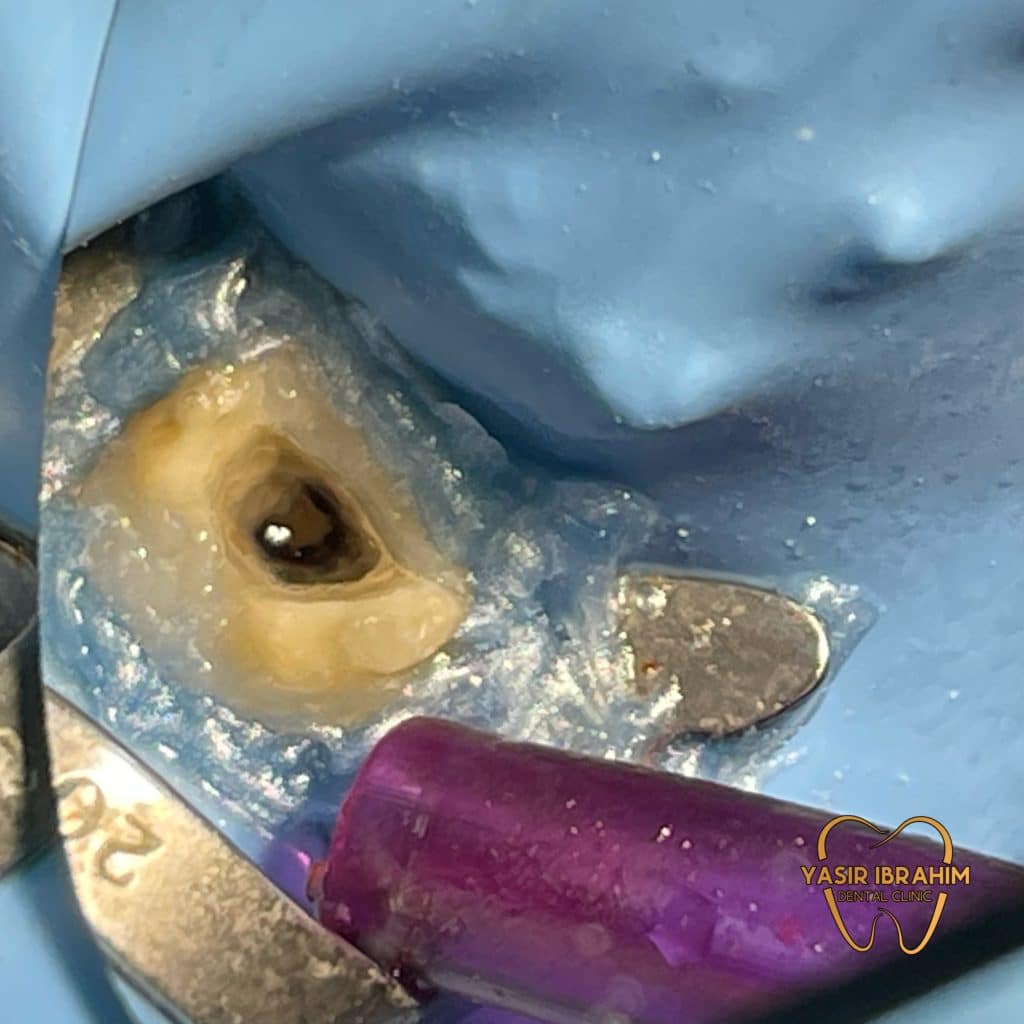

obturation with MTA.

intracanal medicament Ca(OH)2.

Ca(OH)2 removed after 14 days.